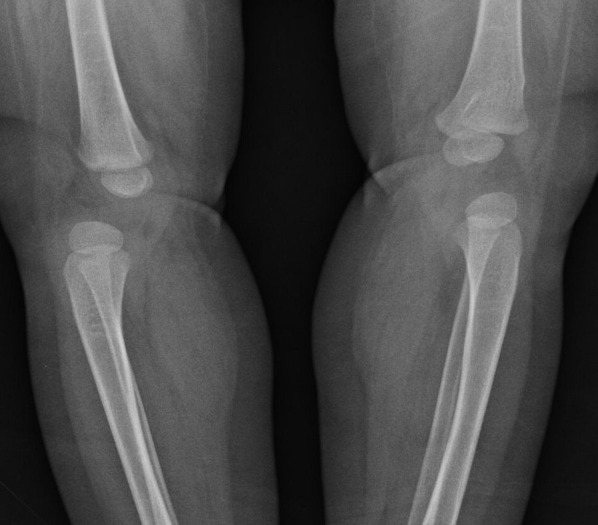

Clinical case: Female patient, one year and three months old, presents hyperextension of the knees. On physical examination, the patient presents bilateral cleft palate, absence of soft palate, cleft lip and tracheostomy, positive Hart sign, negative Peter Bade sign and fixed retrocurved knees with limited range of motion. Radiographs reveal bilateral hip dislocation and knee dislocation. Karyotype analysis confirms the diagnosis of CdCS.